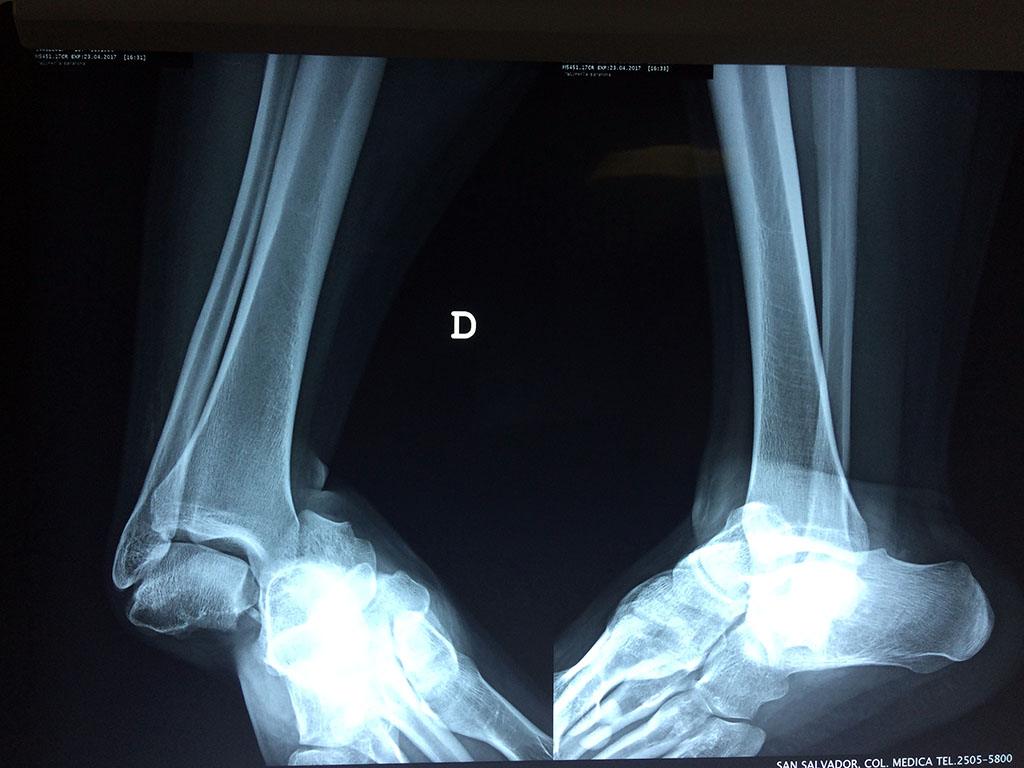

Una fractura de tobillo es la rotura de uno o más de los huesos del tobillo. Estas fracturas pueden ser:

Algunas fracturas de tobillo pueden requerir cirugía si:

- Los extremos de los huesos están desalineados entre sí (desplazados).

- La fractura se extiende hasta la articulación del tobillo (fractura intra-articular).

- Los tendones o ligamentos (tejidos que sujetan los músculos y los huesos entre sí) están rotos.

- El médico cree que sus huesos probablemente no sanen apropiadamente sin cirugía.

- El médico considera que la cirugía puede permitirle una recuperación más rápida y confiable.

- En los niños, la fractura involucra la parte del hueso del tobillo donde el hueso está creciendo.